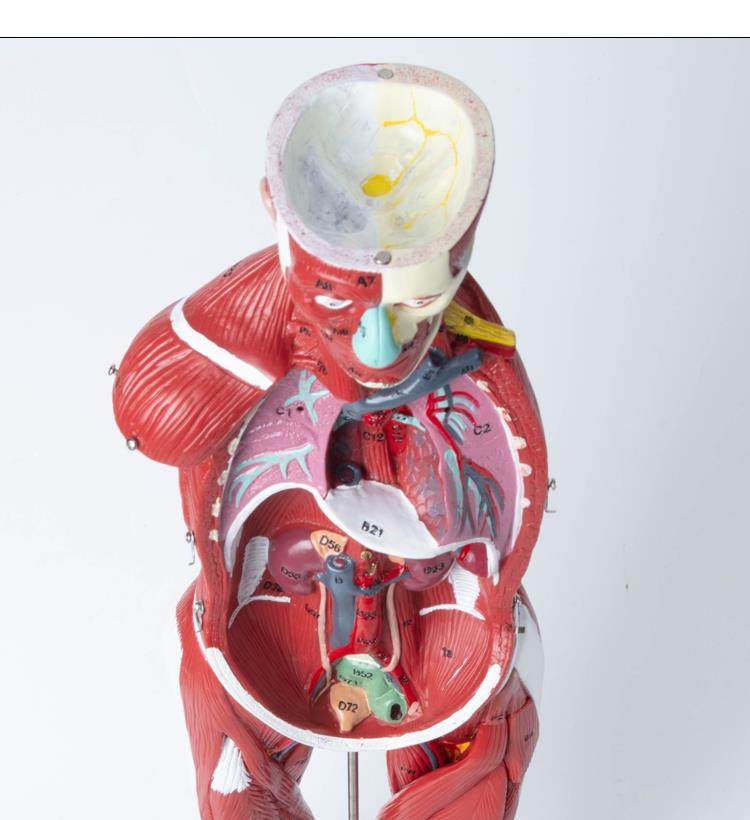

Human Body Muscle Internal Organ Disassembly Anatomy Structure Model Tissue Exercise Artificial Medical Teaching Aids

| Product Specifications | |

| Brand | No Brand (No Registered Trademark) |

| Model | 6622 |

| Color Classification | 85 Human Muscle Internal Organs Removable Organ,50cm Muscle Model |